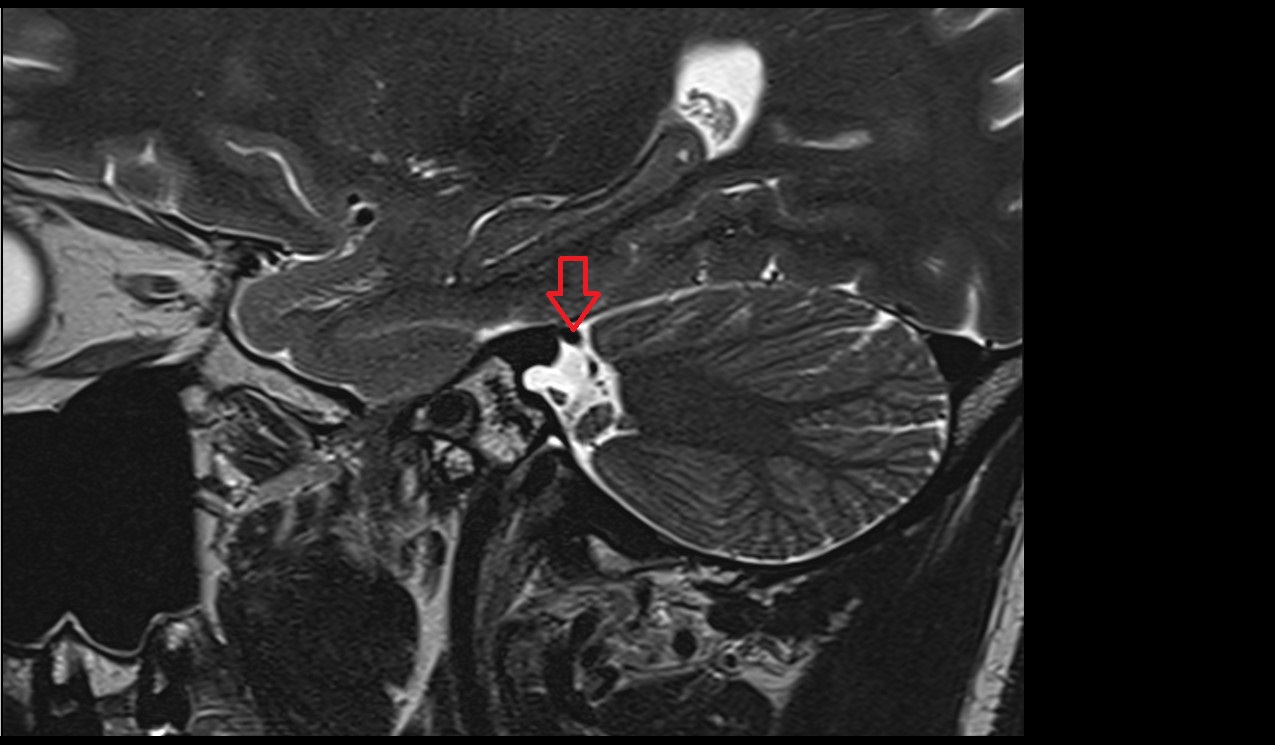

- Cerebellum